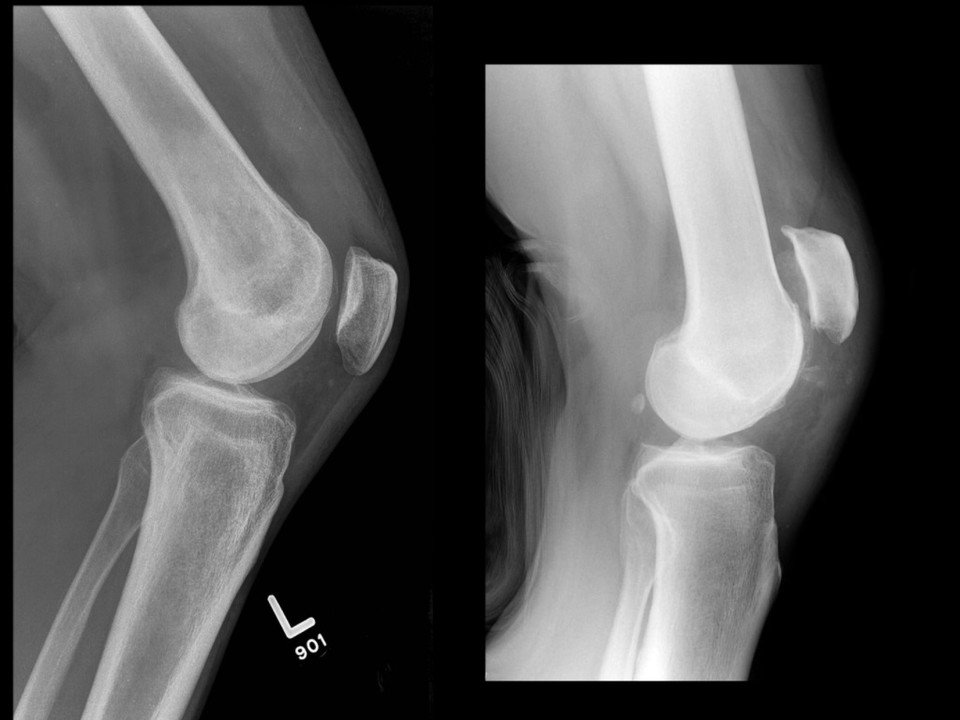

Patellar Tendon Rupture

A patellar tendon rupture is a serious injury affecting the tendon that connects the kneecap (patella) to the shinbone (tibia). This tendon plays a vital role in straightening the leg and stabilising the knee joint during activities such as walking, running, and jumping. A rupture can significantly impair mobility, making it difficult or impossible to straighten the knee or bear weight on the affected leg. Prompt diagnosis and treatment are essential to restore knee function and prevent long-term complications.

A patellar tendon rupture occurs when the tendon connecting the patella to the tibia is torn. This can be a partial tear, where some tendon fibres remain intact, or a complete rupture, where the tendon is entirely severed. A complete rupture typically requires surgical intervention to reattach the tendon and restore full knee function.

- A visible gap or indentation below the kneecap.